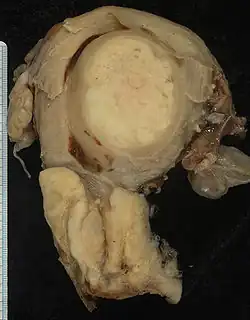

Pathologie

Die Mehrheit aller invasiven Zervixkarzinome sind Plattenepithelkarzinome (80 Prozent), gefolgt von den Adenokarzinomen (5–15 Prozent). Bevorzugter Entstehungsort ist die sogenannte Transformationszone, in welcher das Plattenepithel der Portio auf das Zylinderepithel des Zervix trifft.[21] Andere Tumorformen, wie Adenokankroide, adenosquamöse und mukoepidermoide Karzinome, sind selten. Als Besonderheit treten, ebenfalls selten, sogenannte Gartnergangkarzinome auf. Sie gehen vom Gartnerschen Gang, einem kleinen Teil des rückgebildeten Wolffschen Ganges, aus. Da sich dieser Tumortyp in der Tiefe entwickelt und erst im Verlauf in den Gebärmutterhalskanal durchbricht, hilft die übliche Früherkennung hier nicht.[20] Sarkome der Gebärmutter können sehr selten auch die Zervix befallen.[22] Eine Sonderstellung nehmen dabei die Müllerschen Mischtumoren ein, bei denen karzinomatöse und sarkomatöse Komponenten im gleichen Tumor auftreten. Auch sie befallen eher den Gebärmutterkörper als die Zervix.[23]